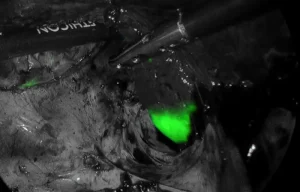

ICG(インドシアニングリーン)蛍光法

当院ではICG(インドシアニングリーン)と呼ばれる特殊な薬剤を使用する手術を実施しています。ICGは血液中のタンパク質と結合する性質があり、特別なカメラを通して見ると緑色に光ります。肉眼では見えにくい情報を可視化することで、より正確に腫瘍やリンパ節の位置または範囲を確認し、精緻で確実な手術を実施しています。これにより合併症リスクの低減や、一層の低侵襲化を図っています。

ICGによる蛍光発色の様子